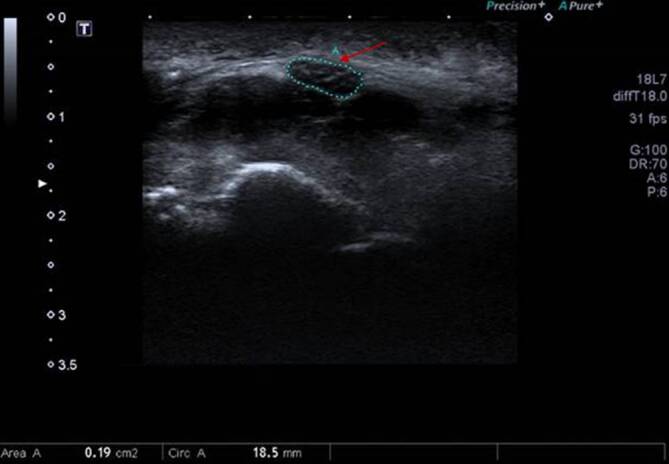

Immune checkpoint inhibitors (ICIs) are successfully used in multiple malignant diseases. Their spectrum of adverse effects includes dermatological, endocrinological, gastrointestinal, and hepatic toxicities, as well as rare neurological side effects affecting the central nervous system and more frequently the peripheral nervous system. Pre-existing neurological disorders may deteriorate. Bilateral carpal tunnel syndrome (CTS) rarely occurs. In the present case, an 83-year-old patient with stage IIIC malignant melanoma (MM) developed pain, swelling, and paresthesia in both hands after five adjuvant therapy cycles with pembrolizumab 200 mg. Following the diagnosis of bilateral CTS, pulse therapy with prednisolone was initiated and subsequently reduced to a maintenance dose of 20 mg orally. Despite the necessary escalation of ICI therapy to ipilimumab/nivolumab due to MM progression, CTS improved under concomitant prednisolone therapy and physiotherapy.

Abstract Image